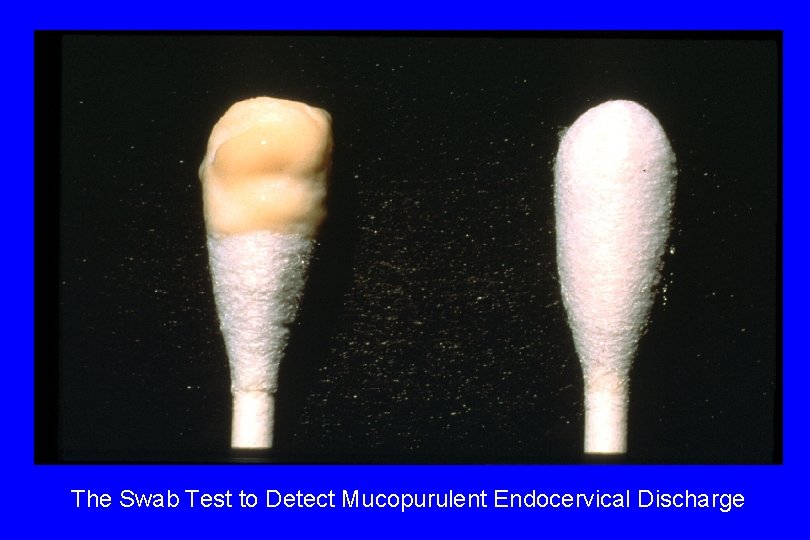

Diagnosis of Cervicitis · · Signs: specific, but insensitive. Include: - easily induced bleeding (“friability”) “Endocervicitis” - mucopurulent discharge: swab test - edematous ectopy - discrete lesions (ulcers): can occur anywhere Increased PMN (“polys; ” >10 -30/HPF) on Gram stain of endocervical secretions: may be sensitive for endocervicitis, but not specific; variable in ectocervicitis

The Swab Test to Detect Mucopurulent Endocervical Discharge